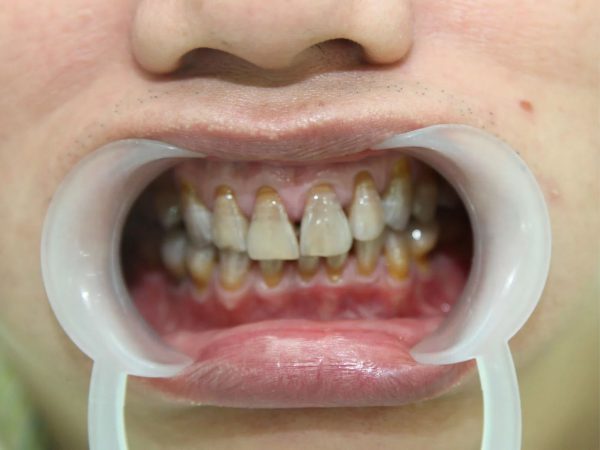

Anh Bill Huỳnh – Hành trình tìm lại nụ cười rạng rỡ cùng Platinum Dental Group

Từng mặc cảm vì hàm răng nhiễm Tetracycline cấp độ 4 – mức nặng nhất, anh Bill Huỳnh (Australia) đã tìm đến Platinum Dental Group để tìm lại nụ cười tự tin. Tình trạng răng xám vàng kéo dài nhiều năm khiến anh ngại giao tiếp, ảnh hưởng không nhỏ đến công việc và cuộc sống.

Sau khi được Dr. Lan Anh trực tiếp thăm khám, anh được chỉ định giải pháp Răng sứ thẩm mỹ toàn diện hàm trên và hàm dưới. Kết quả mang lại sự thay đổi vượt ngoài mong đợi:

- Răng trắng sáng, tự nhiên, loại bỏ hoàn toàn vết nhiễm màu nặng.

- Dáng răng – cung cười đạt tỉ lệ vàng, hài hòa với gương mặt

- Thần thái trẻ trung, gương mặt rạng rỡ và cuốn hút hơn.

Hoàn tất điều trị, anh Bill chia sẻ cảm giác như được “tái sinh”: thoải mái cười tươi, tự tin xuất hiện trong mọi khoảnh khắc. Với Platinum Dental Group, mỗi ca phục hình không chỉ là cải thiện thẩm mỹ, mà còn là hành trình đồng hành để kiến tạo một phiên bản rực rỡ hơn của chính bạn.

Hoàn tất điều trị, anh Bill chia sẻ: “Tôi chưa bao giờ nghĩ mình có thể sở hữu một hàm răng trắng sáng đến vậy. Trước đây, tôi luôn tránh cười, còn bây giờ tôi cảm thấy như được sống một cuộc đời mới tự tin, thoải mái và hạnh phúc hơn rất nhiều. Cảm ơn Platinum Dental Group và bác sĩ Lan Anh đã mang lại cho tôi nụ cười này.”